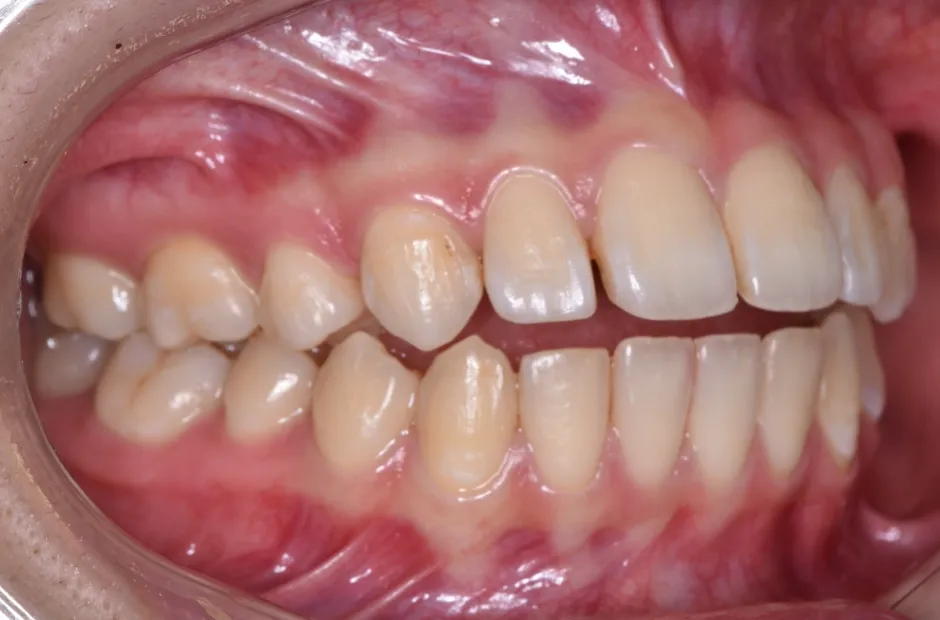

受け口(反対咬合・下顎前突)

下顎の歯が上顎の歯より前に突き出ている状態です。通常は上顎の前歯が下顎の前歯に少しだけ覆い被さる形になりますが、それが逆になっています。横顔のラインが崩れるだけでなく、食事や発音に支障をきたしやすくなります。特にお子様の場合は成長とともに状態が悪くなることが多いため、早期改善が重要です。矯正治療で上下の顎のバランスが整うと、顔全体のバランスも整い、食事や発音の問題も改善されます。

受け口

| 診断名・主訴 | 反対咬合 |

|---|---|

| 年齢・性別 | 42歳・男性 |

| 治療期間・回数 | 2年 16回 |

| 治療に用いた主な装置 | シュアスマイル |

| 抜歯部位 | なし |

| 治療費 | 80万円(税抜) |

| リスク・副作用 | 装置による違和感・疼痛・歯肉退縮・歯根吸収・虫歯のリスクなど |

治療前

治療後